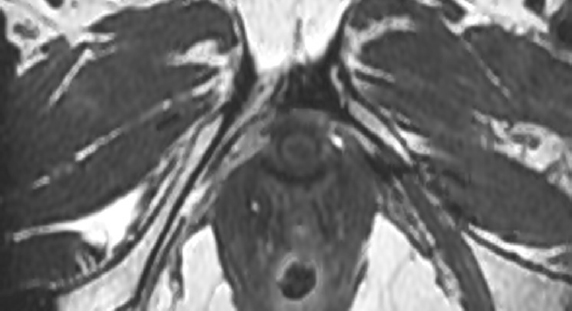

Результаты МРТ, выполненной для оценки функциональной адаптации комбинированного слинга, демонстрируют процессы биологической трансформации аллотрансплантата уже через 3 мес. (рис. 5), а через 6 мес. после операции — инициацию процессов ремоделирования.

Рис. 5. Магнитно-резонансная томограмма органов малого таза через 3 мес. после операции. Стрелкой указана локализация аллотрансплантата